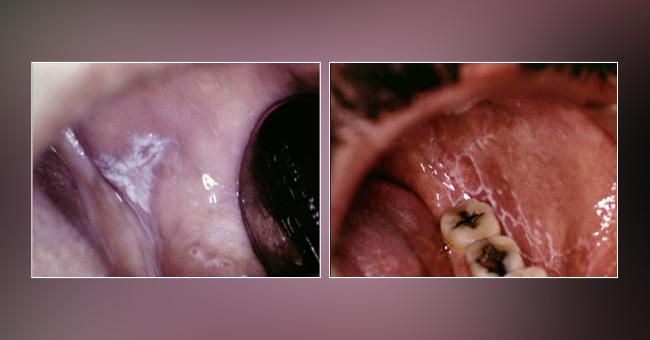

White Lesions

Six Clinical Types Of Oral Lichen Planus Olp On The Oral Mucose